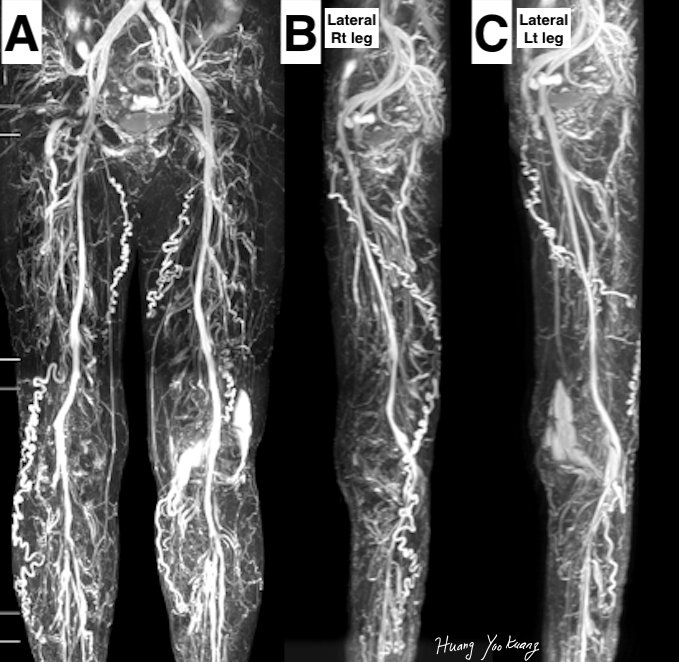

明顯的骨盆充合併骨盆腔滲漏及雙足靜脈曲張。

我們可以從正面同時看到兩條腿有的骨盆腔滲漏,需要單腿模式才可以看清楚滲漏的正確走向。(B.C.)